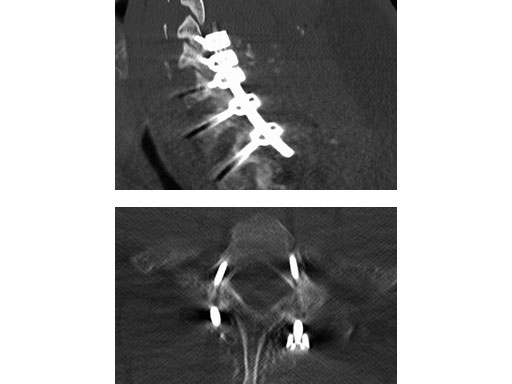

A 28-year-old, 109 kg man was involved in a high-speed motor vehicle collision with C7-T1 jumped facet and T1 teardrop fracture. The patient had ASIA E with motor score of 100. He had failed closed reduction in the emergency room then was taken to OR emergently for open reduction and C5-T2 posterior segmental instrumentation with synapse 4.0. The patient did well postoperatively with no evidence of collapse or failure.

Synapse 4.0 was the ideal solution to treat this injury. This was a heavy patient with a highly unstable injury at the cervicothoracic junction. Synapse 4.0 enabled stabilization of his injury with a rigid construct. It has all the benefits of the 3.5 system but is more rigid and allowed use of one system as opposed to using the 3.5 system and a 6.0 rod system with the nuances of a tapered rod. The author was able to place C5 and C6 lateral mass screws utilizing the Magerl technique and C7, T1, and T2 pedicle screws.